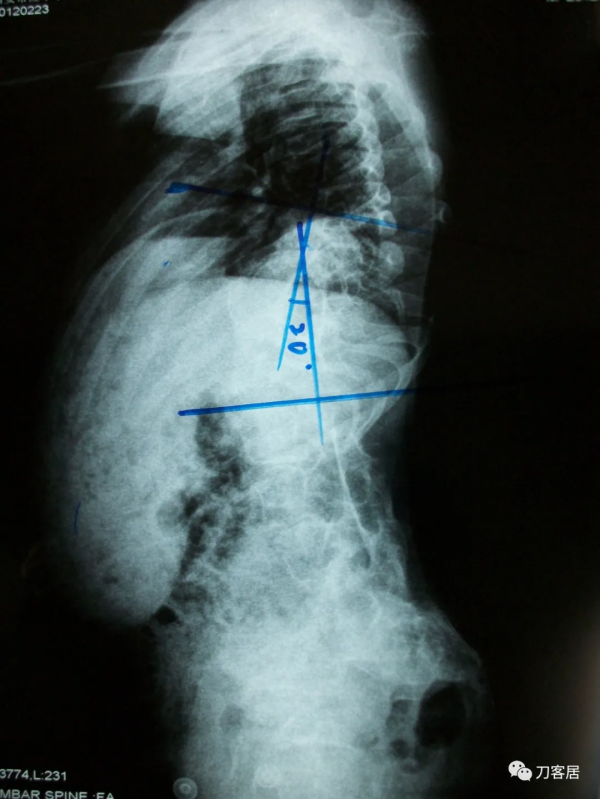

入院診斷:1.先天性脊柱側彎畸形;2.低位脊髓,脊髓栓系。入院後查血常規:WBC 4.30×109/L,RBC 4.83×1012/L,L 41.94%,N 46.54%,HB 134g/L,HCT 41.5%,PLT 295×109/L。尿常規示:PH 5.0,尿比重1.020。糞常規及潛血:正常。凝血四項:PT 12.7s,INR 1.02s,APTT 31.42s,TT 16.20s,FIB 2.27g/L。肝功:AST 32.3u/L,ALT 37.2,TBIL 11.3,IDBIL 7.6,DBIL 3.7,TP 72.3,ALB 45.2,GLO 27.1。腎功電解質:Urea 5.45mmol/L,Cr 51.6umol/L,UA 120.2umol/L,HCO 324.1mmol/L,K+ 3.95mmol/L,Na+ 137.9mmol/L,CI+ 99.1mmol/L,Ca+ 2.25mmol/L。心電圖:竇性心律,心電圖大致正常。胸部X線片:脊柱側彎,胸廓畸形,心肺膈未見異常。腰椎X線片:脊柱生理曲度消失,腰段脊柱向左側凸起,胸10為上端椎,腰5為下端椎,側凸85°,椎體旋轉II°至III°。胸段脊柱向右側突,以胸2為上端椎,胸10為下端椎,側凸90°,胸腰段輕度後凸畸形,Risser徵0級。胸11-腰1椎體分節不全,胸12及腰1及腰2-骶1附件融合。以腰1椎體為中心腰椎向右側凸出。腰1-2椎間隙增寬。診斷結果:先天性脊柱側彎畸形。MRI檢查:胸椎向右側彎曲,所見多胸椎體楔形變,多胸椎間隙不等寬:諸胸椎間盤未見明顯後凸;腰椎脊髓側彎,脊髓位置較低,約平腰3-4水平與硬囊關係緊密。診斷意見:脊柱側彎畸形,脊髓低位,脊髓栓系。心臟超聲檢查:EF55%,心內結構未見明顯異常,左室收縮功能正常,舒張期順應性好,彩色血流未見明顯異常。肺功能檢查:輕度混合型通氣障礙。VC 72%,FEV1 62%, MVV 46%。雙下肢神經電生理報告:DSEP:右側T8、L4,左側T12,雙側T10皮節-皮節P1波潛伏期延長。左側右側雙側皮節內踝-皮層波潛伏期延長。右側L2、5皮節-皮層P1波波幅較對側降低50%以上。視誘發電位CVEP示:雙眼視神經傳導大致正常。

患者術前